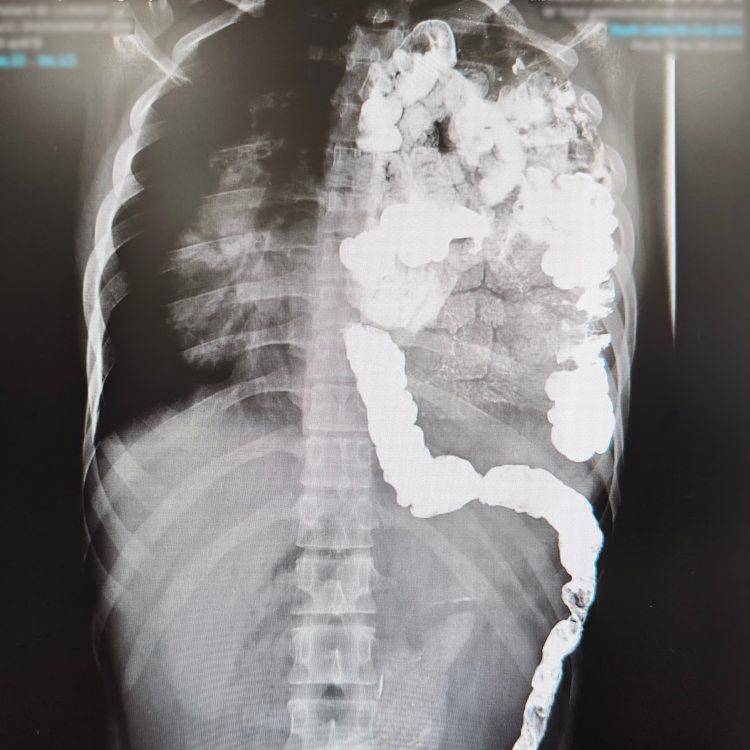

醫院檢查發現,男孩左肺有感染,且腸道大部分侵佔在胸腔裡,需要手術治療。男孩隨後轉至重慶醫科大學附屬兒童醫院進一步治療,醫生隨後解釋「這個疾病叫先天性膈疝,孩子大部分腸子都跑到胸腔裡了,嚴重擠壓著心臟和左肺。」這也是他第一次接診如此大年齡的先天性膈疝患兒,腸道壓迫了左肺才是男孩一直咳嗽的根源,「先天性膈疝並不少見,診斷也不複雜,目前產前即可診斷,一般出生后就需要處理,以往我們接診的患兒最大不過四五歲。」

什麼是先天性膈疝?正常情況下,人體的腹腔和胸腔之間有一個分隔結構,稱之為膈肌。如果胎兒期的膈肌發育異常,閉合不全,膈肌上有一個腹腔里的臟器通過膈肌缺損疝入胸腔,擠占胸腔里肺和心臟的空間,對肺和心臟形成壓迫,這就是先天性膈疝,「缺損最常見於膈肌後外側,這名男孩就屬於這一種。」。